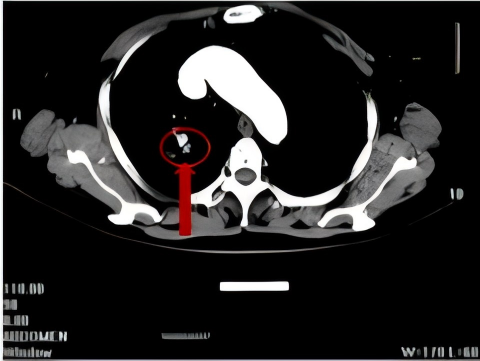

2011年,一名70岁患者因出现咳嗽、咳痰带血等症状就诊于我院呼吸门诊,在完善CT等相关检查后,患者被诊断为右上腺癌(多原发),在充分的与患者及家属进行沟通后,明确表示不接受外科手术,科室为患者制定并实施了CT引导下经皮肺穿刺射频消融+碘125粒子植入放疗+化疗的治疗方案。

术 前

术 后

患者分别在治疗4月和1年后复查胸部CT显示病灶稳定,病情得到进一步控制。

术后4月复查

术后1年复查